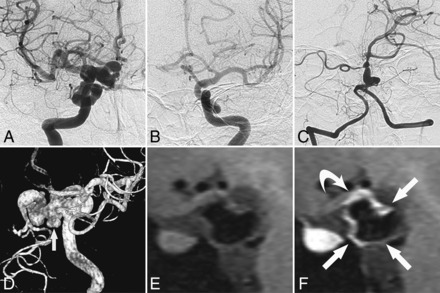

All patients had the unique feature, segmental elongation and tortuosity of the distal ICA, resulting in a tangled arterial mass (Fig 2). No differences were observed between the sides of onset (right, 11/20). Two patients presented with bilateral distal ICA dolichoectasia. In these 2 patients, we defined the side with more severe dolichoectasia as the ipsilateral side, while the other side was the contralateral side. The involved ICA segments ranged from segments 2 to 7, with a mean ± SD of 3.5 ± 1.6 segments. Fourteen patients had BA (n = 1) or ipsilateral PCA (n = 13) involvement [BA/PCA (+)]. We observed a significant correlation between ipsilateral A1, PcomA, BA/PCA, and midbrain hypoplasia and segmental ICDE of the distal ICA, unlike the contralateral side (Table 1).

Representative images of ICDE in a patient without PHACE syndrome (patient 6, a 28-year-old woman). A and B, Bilateral ICA angiography shows a tangled arterial mass of the left distal ICA and no observable left A1 segment. C, Left vertebral artery angiography shows a dolichoectasia of the left P1 and P2 segments (arrow). D, CT angiography shows hypoplasia of the left A1 segment (arrow). E, T2-weighted image of the brain shows hypoplasia of the left midbrain. F, CT image of vessel wall calcification in the left distal ICA (arrow).